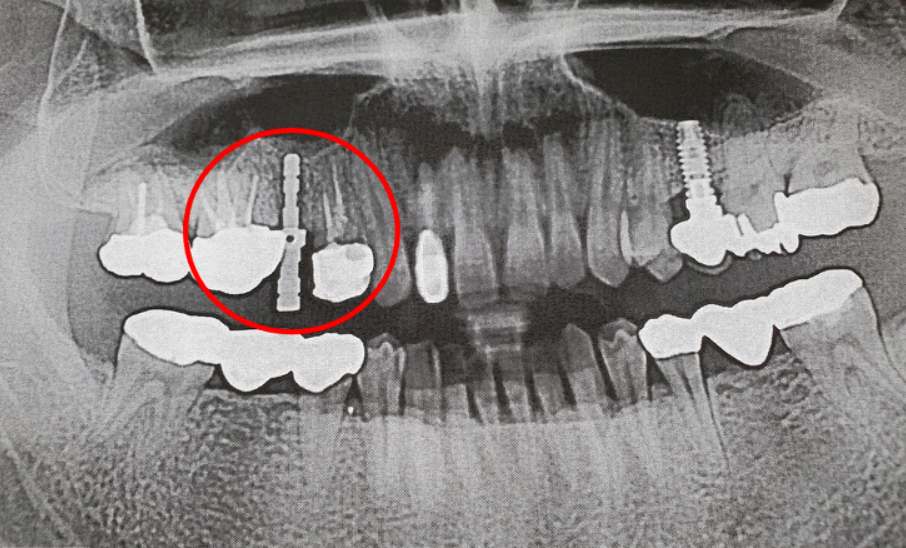

일반적으로 우리가 상악동 거상술을 하는 이유는 임플란트 삽입을 위해서 일겁니다. 부비동 확대라고도하는 상악동 거상술은 치과 임플란트를 더 쉽게 배치 할 수있는 시술입니다. 일부 환자는 염증과 같은 이유로 뼈가 손실되어 임플란트에 필요한 뼈 지원 받아야 합니다. 우리는 이를 치조골 이식이라고 보통 이야기 합니다.

치조골 이식은 치과 임플란트에 필요한 상악뼈의 양을 증가시킵니다. 치과 임플란트 환자에게 가장 일반적인 골이식 절차중 하나이며, 혹시나 예전에 종신보험을 들어놓으신 분들은 특약으로 들어놓은 2종수술에 치조골 수술이 들어가 있는 한번 살펴보시기 바랍니다. 아래에 다시 이야기 드릴게요.

뼈 출처가 확인되면 치과 전문의가 턱과 부비동의 상황을 파악하기 위해 세심한 주의를 가지고 기존 뼈의 높이와 너비를 평가하고 부비동을 평가하기 위해 정확한 측정이 이루어집니다. 즉 뼈선택을 마치면 수술날짜를 잡으면 됩니다.